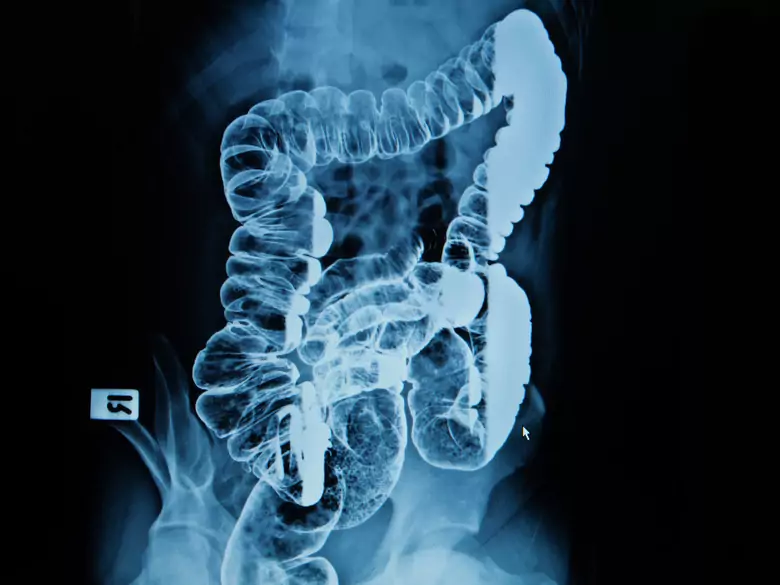

La nutrición enteral es el método fisiológico de nutrición. Este tipo de nutrición es el método de elección en los pacientes que requieren un apoyo nutricional cuando una dieta de alimentos integrales no es capaz de cubrir las necesidades energéticas.